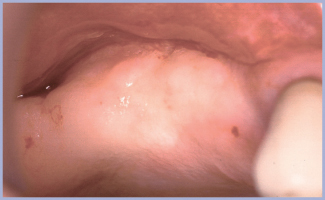

Si rivede il paziente nel giugno 2009 a distanza di 5 anni: come emerge dall’esame clinico (figg. 27, 31) i tessuti appaiono sani e notevolmente migliorati rispetto al tempo della consegna della protesi. Le immagini radiografiche (figg. 28-30, 32) permettono di evidenziare il mantenimento di una corretta osteointegrazione, un aumento verticale di osso a carico della cresta del primo quadrante e, soprattutto, un mantenimento osseo crestale periimplantare ottimale, senza alcun riassorbimento, esattamente sovrapponibile al tempo zero.

- Fig. 27 – Controllo 1° quadrante a 5 anni – anno 2009

- Fig. 31 – Controllo anno 2009, 3° quadrante